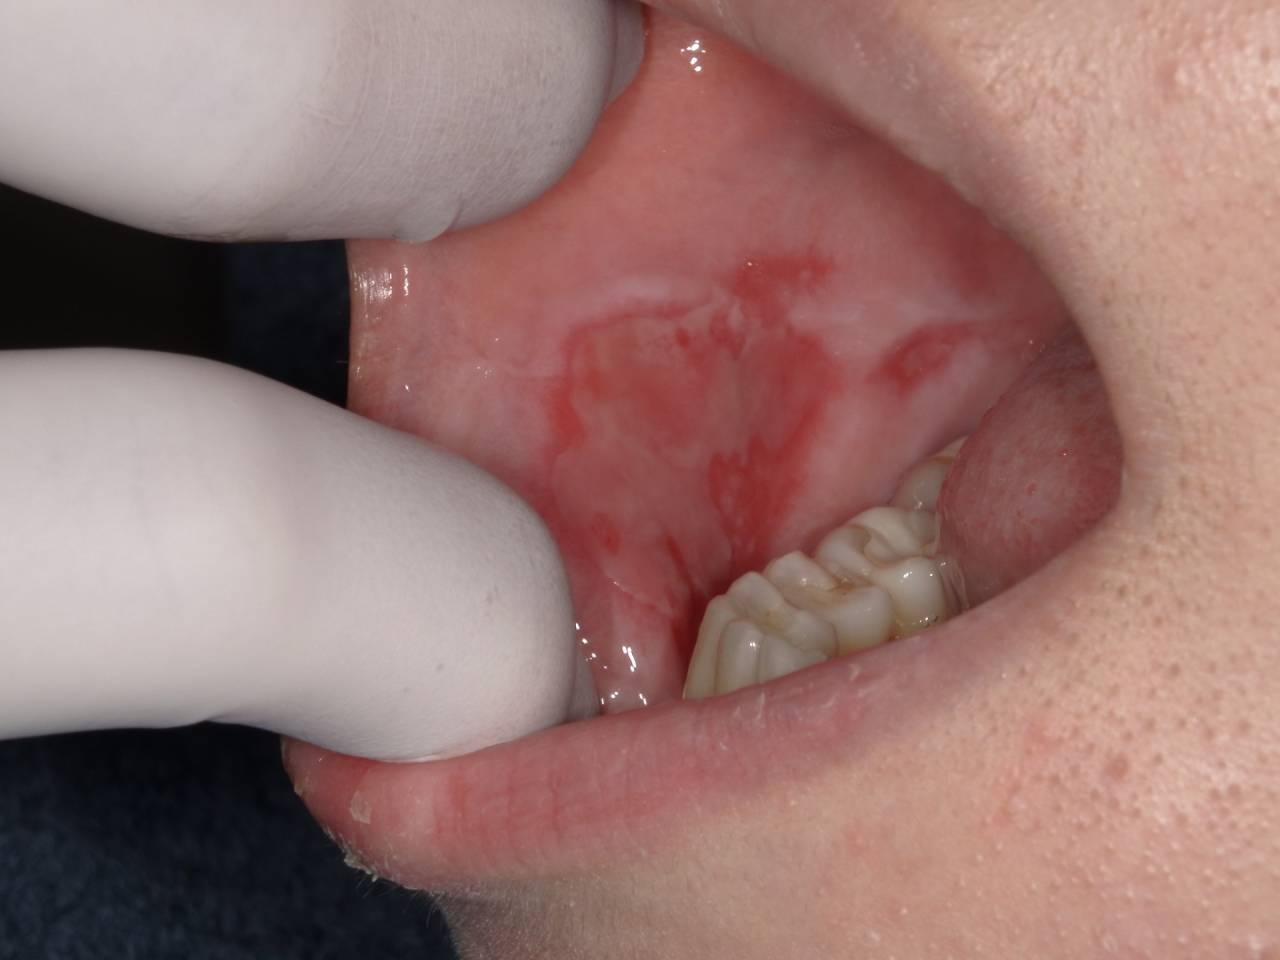

単純疱疹 疱疹性口内炎口腔病理基本画像アトラス。

口内炎を写真で解説診察室でよくみる大人の病気 - みやけ内科・循環器科。